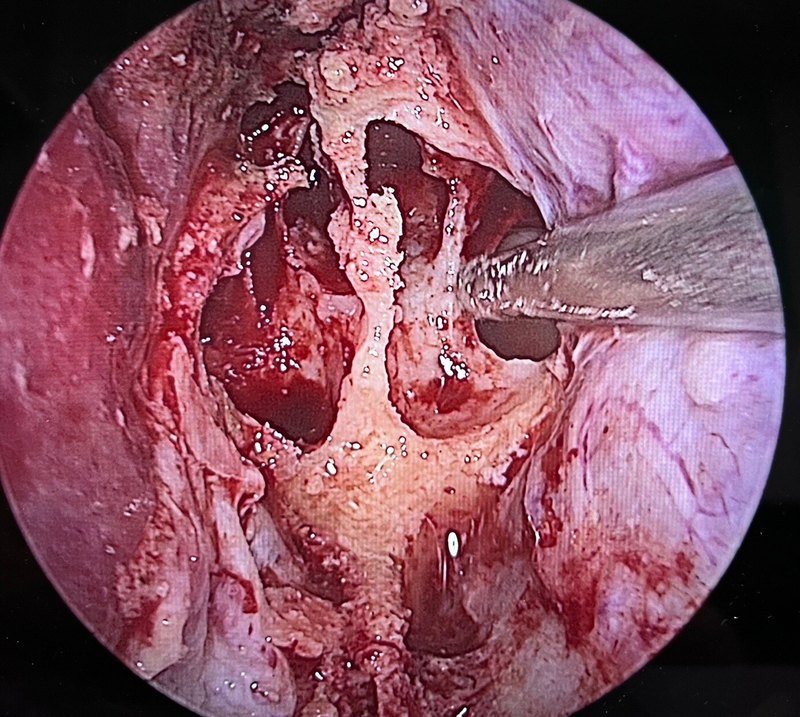

近期第三例因垂體病變導致視力下降(幾近全盲)的病例今天出院了,患者成年男性,因發(fā)熱入住呼吸科,隨后兩天頭痛明顯并視力急劇下降,眼科會診建議排除顱內病變[強][強],轉入我科進一步內分泌檢查示多項激素水平極低,經抗感染,補充激素等處理后患者頭痛,發(fā)熱癥狀消失,視力亦有改善,復查MR提示視神經仍受壓明顯,在神經內鏡經鼻切除病變,術后患者說“整個世界清亮了”